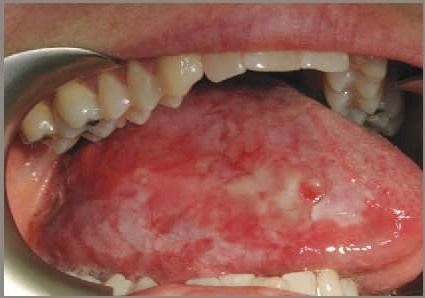

نشانههای اولیه و زودرساین بیماری میتواند شامل لکههای قرمز یا سفید طولانی مدت، زخم همیشگی، تورم رو به رشد، تحرک و جابجایی ناگهانی دندان، خونریزی غیرطبیعی و خستگی طولانی مدت است.

کسانی که در حفره دهان، رو یا زیر زبان یا کنارههای دهان، زخمی را مشاهده میکنند که بیش از دو هفته طول کشیده، اما خوب نشده است یا فَک خود را نمیتوانند به راحتی و خوب حرکت دهند باید به آن توجه و به پزشک مراجعه کنند.

طیف گسترده نشانههایی از قبیل سفت شدن مناطقی از سطح دهان، تغییرات ظاهری دهان و لب، انسداد مسیرهای هوایی، عفونت گوش میانی، گوش درد، گرفتگی عضلات فک، بلع سخت، تورم غدد لنفاوی، درد مقاوم وایجاد مشکل در بینایی فرد میتواند از علائم ثانویه این بیماری باشد.